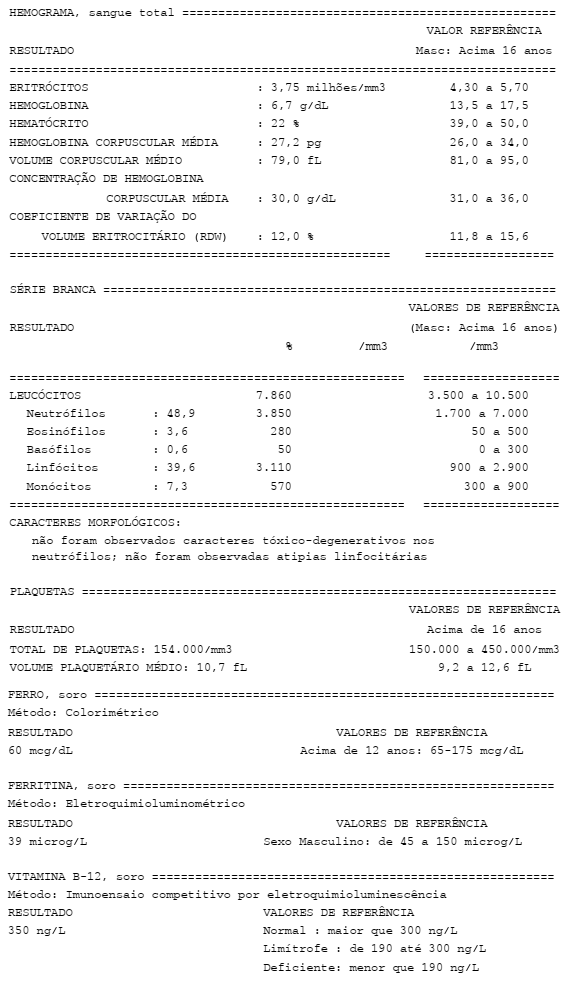

Homem, 66 anos, sem antecedentes mórbidos, refere cansaço aos médios esforços, que se iniciou há 3 meses. Nega sintomas associados, dor abdominal, melena ou enterorragia. Ao exame físico, nota-se o paciente descorado 3+/4+ e eupneico em ar ambiente. PA = 110 x 70 mmHg. As auscultas cardíaca e pulmonar são normais. Os exames laboratoriais relevantes estão ilustrados a seguir.

Assinale a alternativa que contém a abordagem correta nesse caso.